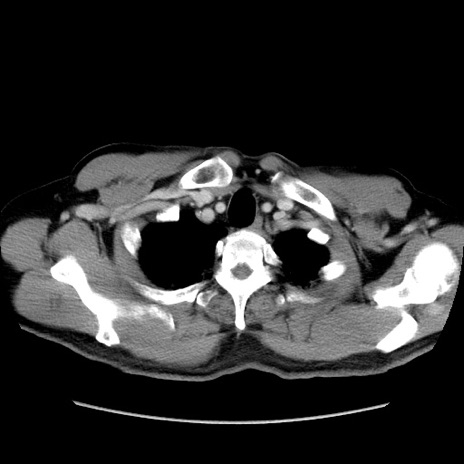

症例34(横断像)

【症例】60歳代 男性

【主訴】右鼠径部膨隆

【現病歴】1年程前より右鼠径部膨隆あり。自己にて還納可能だったため放置していた。3時間前より右鼠径部の脱出を認め、還納困難となり受診。

【身体所見】右鼠径部に小児頭大の膨隆あり。弾性硬であり、用手還納は困難。左鼠径部にも膨隆を認める。脱出はなし。